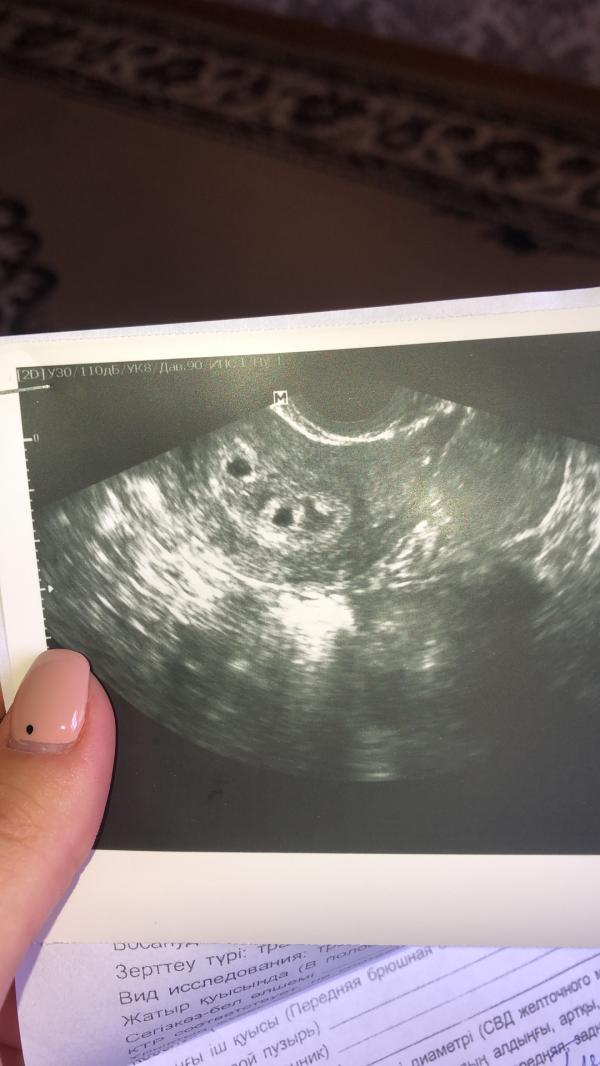

Всем приветик👋🏻Мое первое узи 😇 Сегодня сходила на узи , так как маленький срок сделали вагинальное😬уже неделю побаливает низ живота, чтоб наверняка сходила , долгожданная беременность, пол года ждём , сказали что есть чуток угроза , прописала дюфастон 7 дней ,когда осматривала увидели 2 плода 😇двойняшки , летаю на седьмом небе от счастья, не ожидала , все по воле Всевышнего 😇не удержалась и пишу вам и делюсь 🤗Теперь очень переживаю через 2 недели пойду на узи 🥰

@moms_a, мне на узи 4 недели сразу сказали что ди ди это значит в разных плацентах, а вы сняли узи?